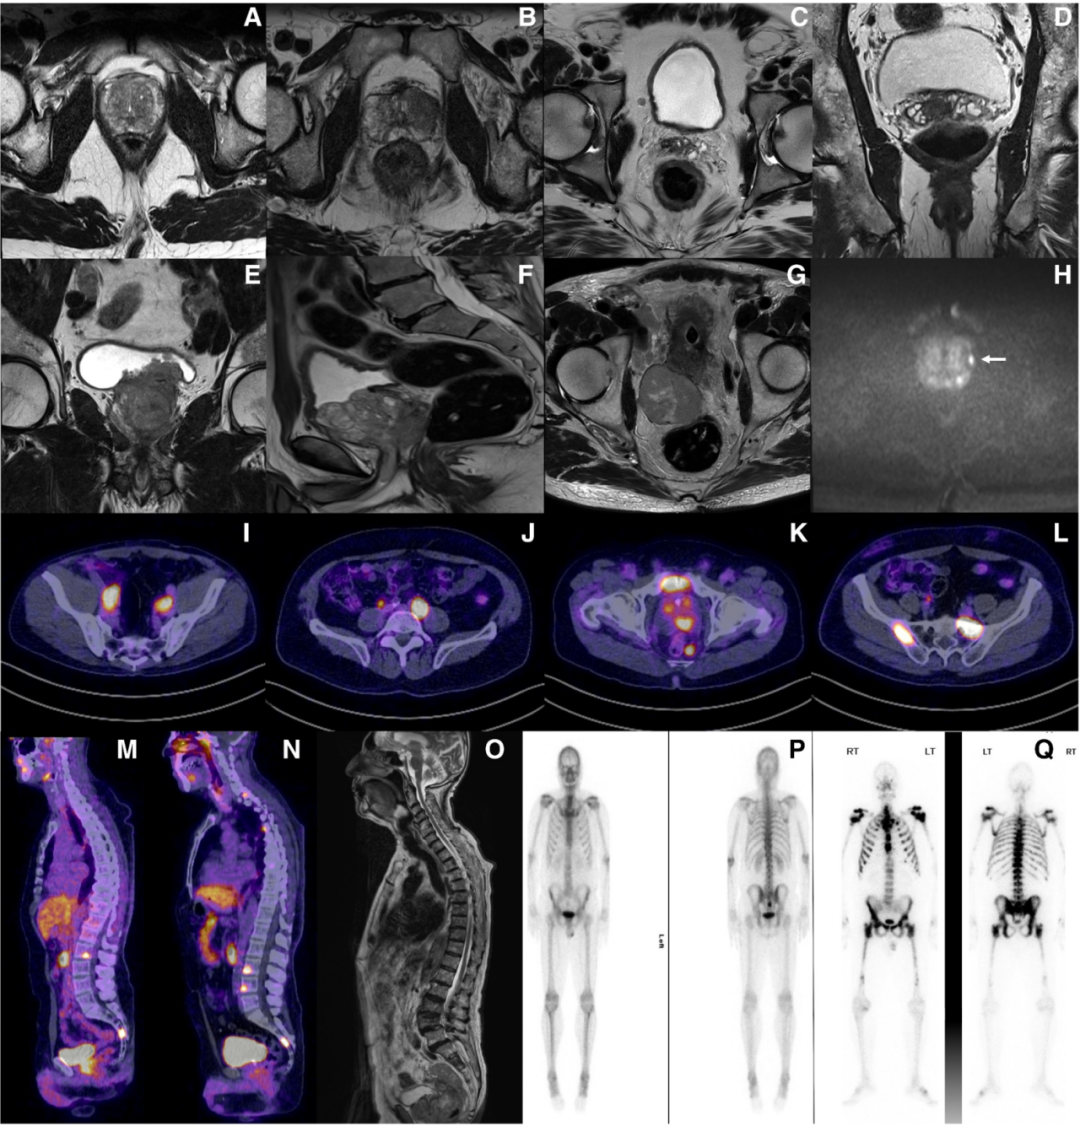

前列腺特异性膜抗原(PSMA)是一种跨膜蛋白,在前列腺癌细胞上过度表达,尽管约10%的前列腺癌可能为PSMA阴性。超过90%的前列腺内病变为PSMA阳性,且其亲和力与肿瘤分级相对应,因此PSMA是诊断和治疗中的优秀工具。PSMA标记的放射性示踪剂与横断面成像结合,是基线分期的优秀工具。PSMA-PET扫描相较于传统成像(CT和骨扫描)具有更高的敏感性和特异性,辐射剂量更低,扫描时间更短,尽管这尚未显示出能改善临床结局。基线PSMA-PET上的淋巴结疾病可能预测中期肿瘤学结局。全身体MRI的敏感性也高于传统成像,特别适用于评估骨转移。作者认为所有高危患者均推荐进行基线PSMA-PET分期,中危患者也可考虑进行。理想情况下,PET扫描应在开始雄激素剥夺治疗(ADT)前进行,因为这可能会影响检测敏感性。

值得注意的是,既往CHAARTED研究基于传统影像学定义高肿瘤负荷为:骨转移灶≥4个,其中≥1个位于脊柱或骨盆之外;或存在内脏转移;或以上两种情况并存。若采用PET影像,目前对肿瘤负荷的判定尚无统一标准。一项回顾性研究显示,以PSMA-PET测得的肿瘤体积40 cm³作为阈值,可获得与CHAARTED标准相似的区分能力(ROC曲线分析)。未来人工智能有望进一步优化该判定方法。PET扫描在淋巴结及骨分期方面较传统影像更为敏感。

△前列腺癌的影像学诊断:前列腺MRI(A-H)、PSMA-PET(I-N)、全身MRI(O)以及骨扫描(P、Q)